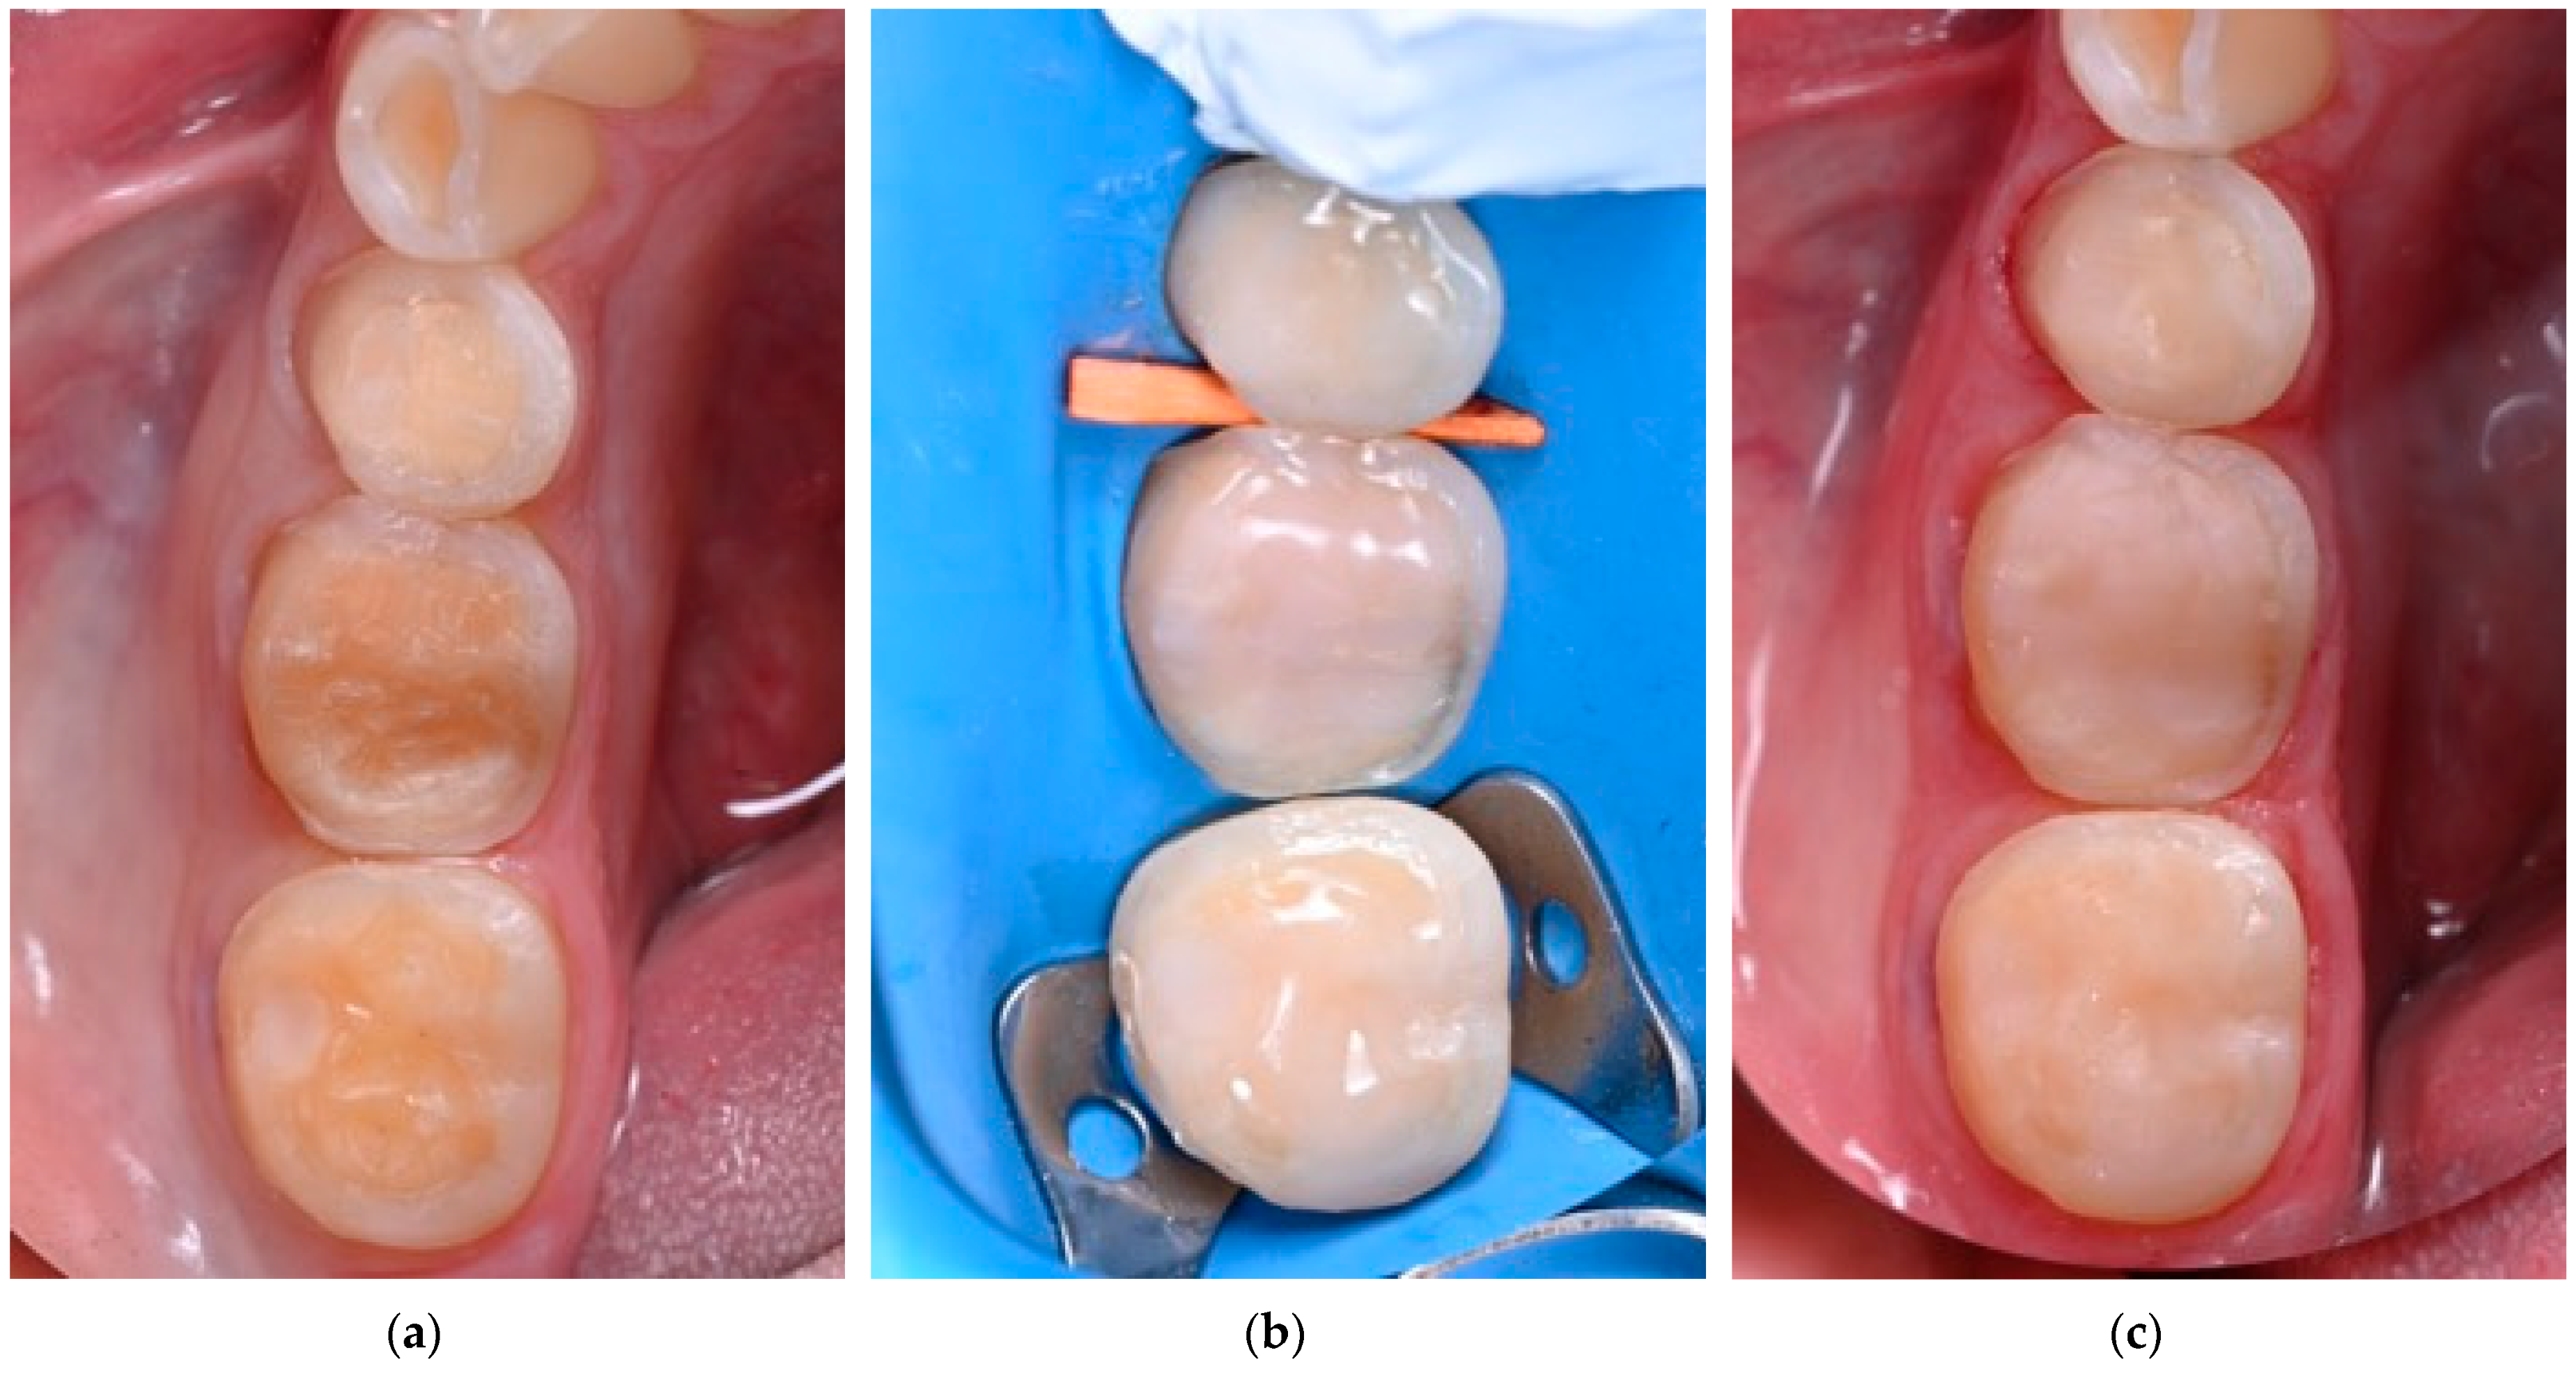

- Fichera, G.; Mazzitelli, C.; Picciariello, V.; Maravic, T.; Josic, U.; Mazzoni, A.; Breschi, L. Structurally Compromised Teeth. Part I: Clinical Considerations and Novel Classification Proposal. J. Esthet. Restor. Dent. 2024, 36, 7–19. [Google Scholar] [CrossRef] [PubMed]

- Fichera, G.; Mazzitelli, C.; Picciariello, V.; Maravic, T.; Josic, U.; Mazzoni, A.; Breschi, L. Structurally Compromised Teeth. Part II: A Novel Approach to Peripheral Build up Procedures. J. Esthet. Restor. Dent. 2024, 36, 20–31. [Google Scholar] [CrossRef] [PubMed]